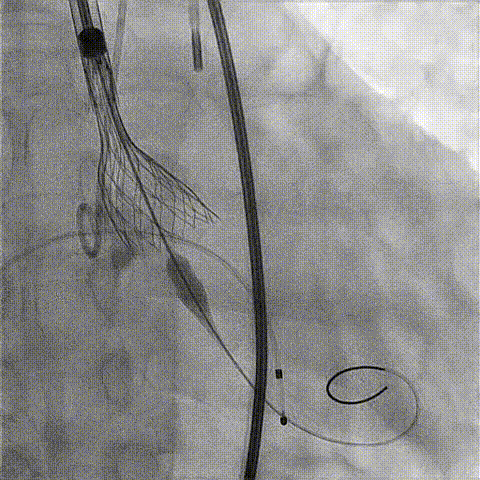

释放工作位造影

后扩后造影

术后超声评估: